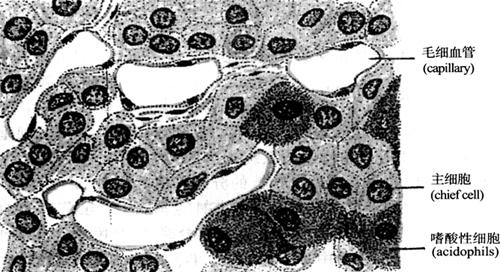

甲状旁腺为黄褐色扁椭圆形小体,位于甲状腺侧叶后面,分为上下两对。每个重约40~60mg。甲状旁腺表面包有薄层结缔组织被膜,腺实质由主细胞(chief cell)和嗜酸性细胞(oxyphilic cell)组成,其间含丰富毛细血管和少量结缔组织(图15-12)。

图15-12 甲状旁腺组织结构

(1)主细胞(chief cell)为圆形或多边形,体积小,核圆居中,细胞质少,染色浅,呈弱嗜酸性。主细胞的功能是合成甲状旁腺素(parathyroid hormone,PTH)。

(2)嗜酸性细胞(oxyphilic cell)体积较主细胞大,为多边形,核染色深,胞质含嗜酸性颗粒,故呈强嗜酸性。此细胞数目较少,但随年龄增大数目有所增加,常单个或成群分布,此细胞功能意义还不是很明确。